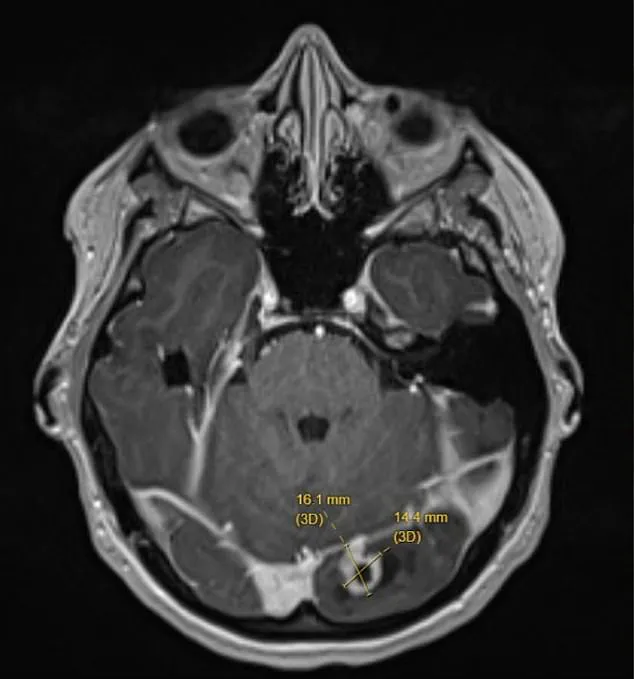

The above is a picture of the scan of Ms Ash’ brain, with the tumor shown by the yellow lines.

Doctors found the tumor on her left occipital lobe — the part of the brain at the back of the head responsible for processing visual information from the right eye.

She was rushed to hospital, where imaging scans revealed a marble-sized tumor pressing on her brain.